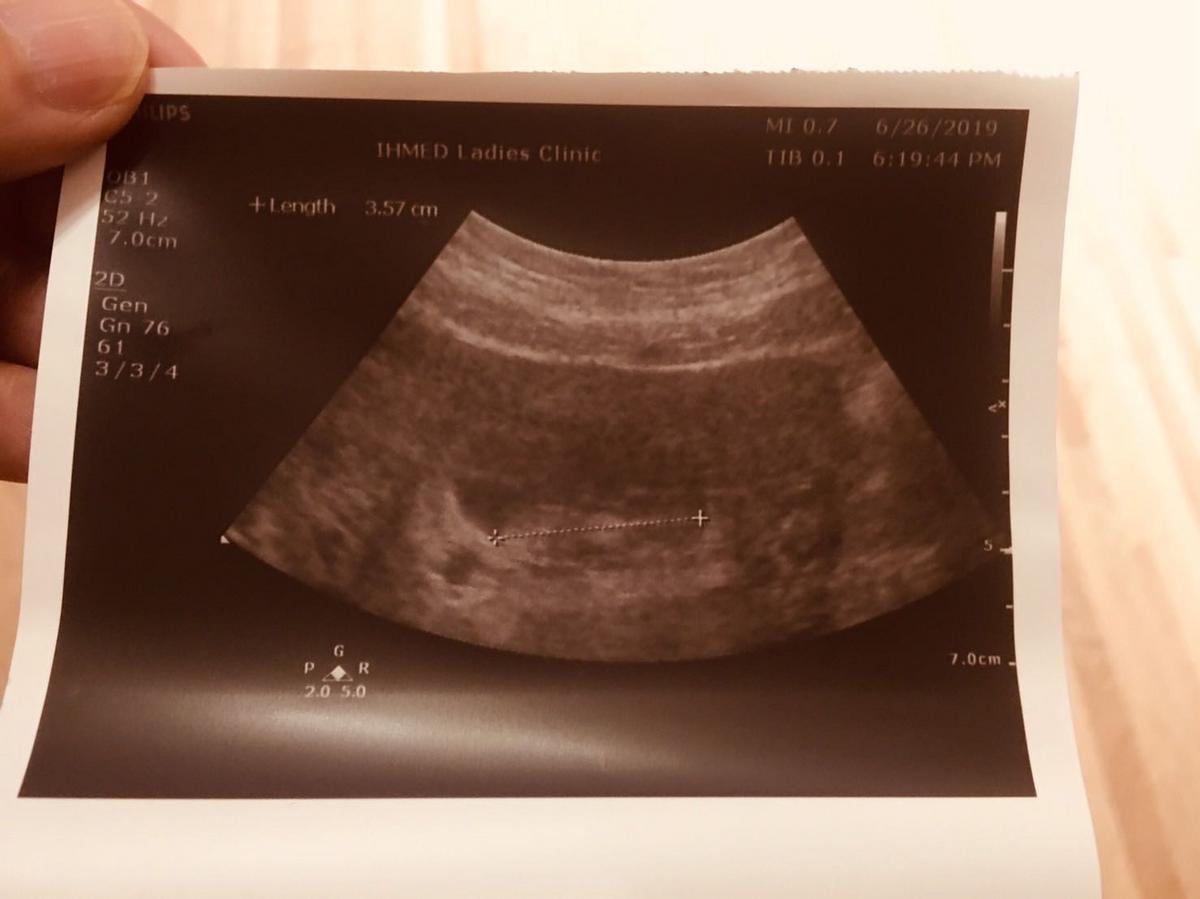

在6月26日給醫生照超音波時有看到妳的手手跟腳腳,而且醫生說妳很活潑的動來動去。說實話媽媽實在是看不出來手腳,但醫生的火眼金睛真的神準啊!

聽到妳很活潑的動來動去媽媽終於安心了一些,看著妳一直在努力的成長,真的很鼓勵媽媽。人們都說懷孕時總是讓人容易感動而且哭點很低,這話真的很準,但相同的因為懷了妳媽媽也變得更加喜樂,看待很多事情的眼光也變得不同。